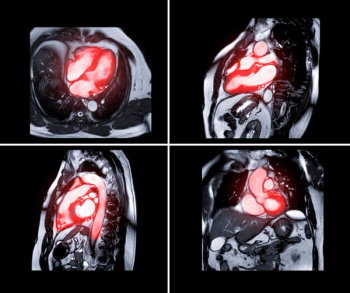

Conditional use of full-body magnetic resonance imaging (MRI) is reportedly permitted for patients using any of the models for the remede® System, an implantable nerve stimulation therapy indicated for the treatment of adults with moderate to severe central sleep apnea.